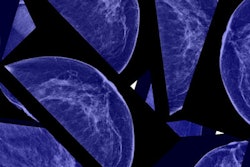

Breast cancer is the leading cause of cancer death among women around the world, Arab Ahmadi noted. Screening for the disease with mammography can be tricky, however: High resolution is needed to identify small lesions, there can be indistinct boundaries on some lesions that mimic normal tissue, and high variation exists among fibroglandular patterns. All of these characteristics can make finding breast cancer with mammography challenging for less experienced readers.

The AI technology improved the AUC and sensitivity of the junior radiologists' reading performance, helping them identify previously missed masses, calcifications, distortions, and asymmetries.